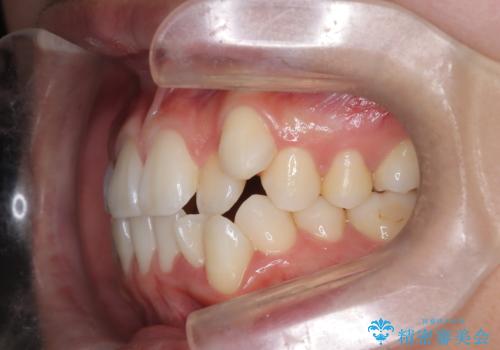

- 治療計画

上下左右の第一小臼歯を抜歯し、クリアブラケット(白い装置)とメタルワイヤーを使用して矯正を開始。初期には犬歯のアーチ内への整列を優先し、中盤からは前歯と奥歯の咬合関係の調整を進めました。審美性に優れた装置を使用したことで、治療中も目立ちにくく、見た目へのストレスが少ない点も評価されています。全体の治療は1年半で完了し、見た目・噛み合わせともに大きく改善。患者本人も「短期間でここまで変わるとは思わなかった」と満足されていました。